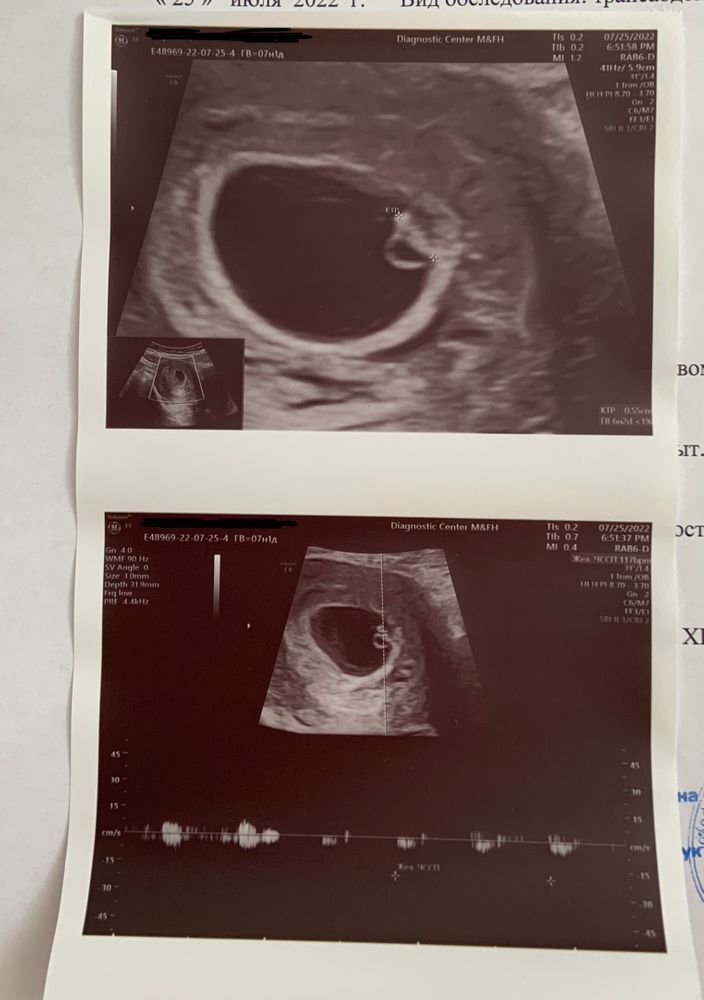

НАШЕ ПЕРВОЕ УЗИ

Беременные СпбВот и состоялась наша первая встреча с крошкой. Вчера 25.07 были на узи вместе с нашим папой!

Наш малыш в матке и у него бьется сердечко ❤️🥺

Срок по последним месячными 7 недель и 1 день.

По УЗИ поставили 6 недель и 2 дня.

КТР 5,5 мм

Сердцебиение 117 уд.в мин.

Желточный мешочек 4,0 мм

Жёлтое тело в правом яичнике до 40 мм в диаметре.